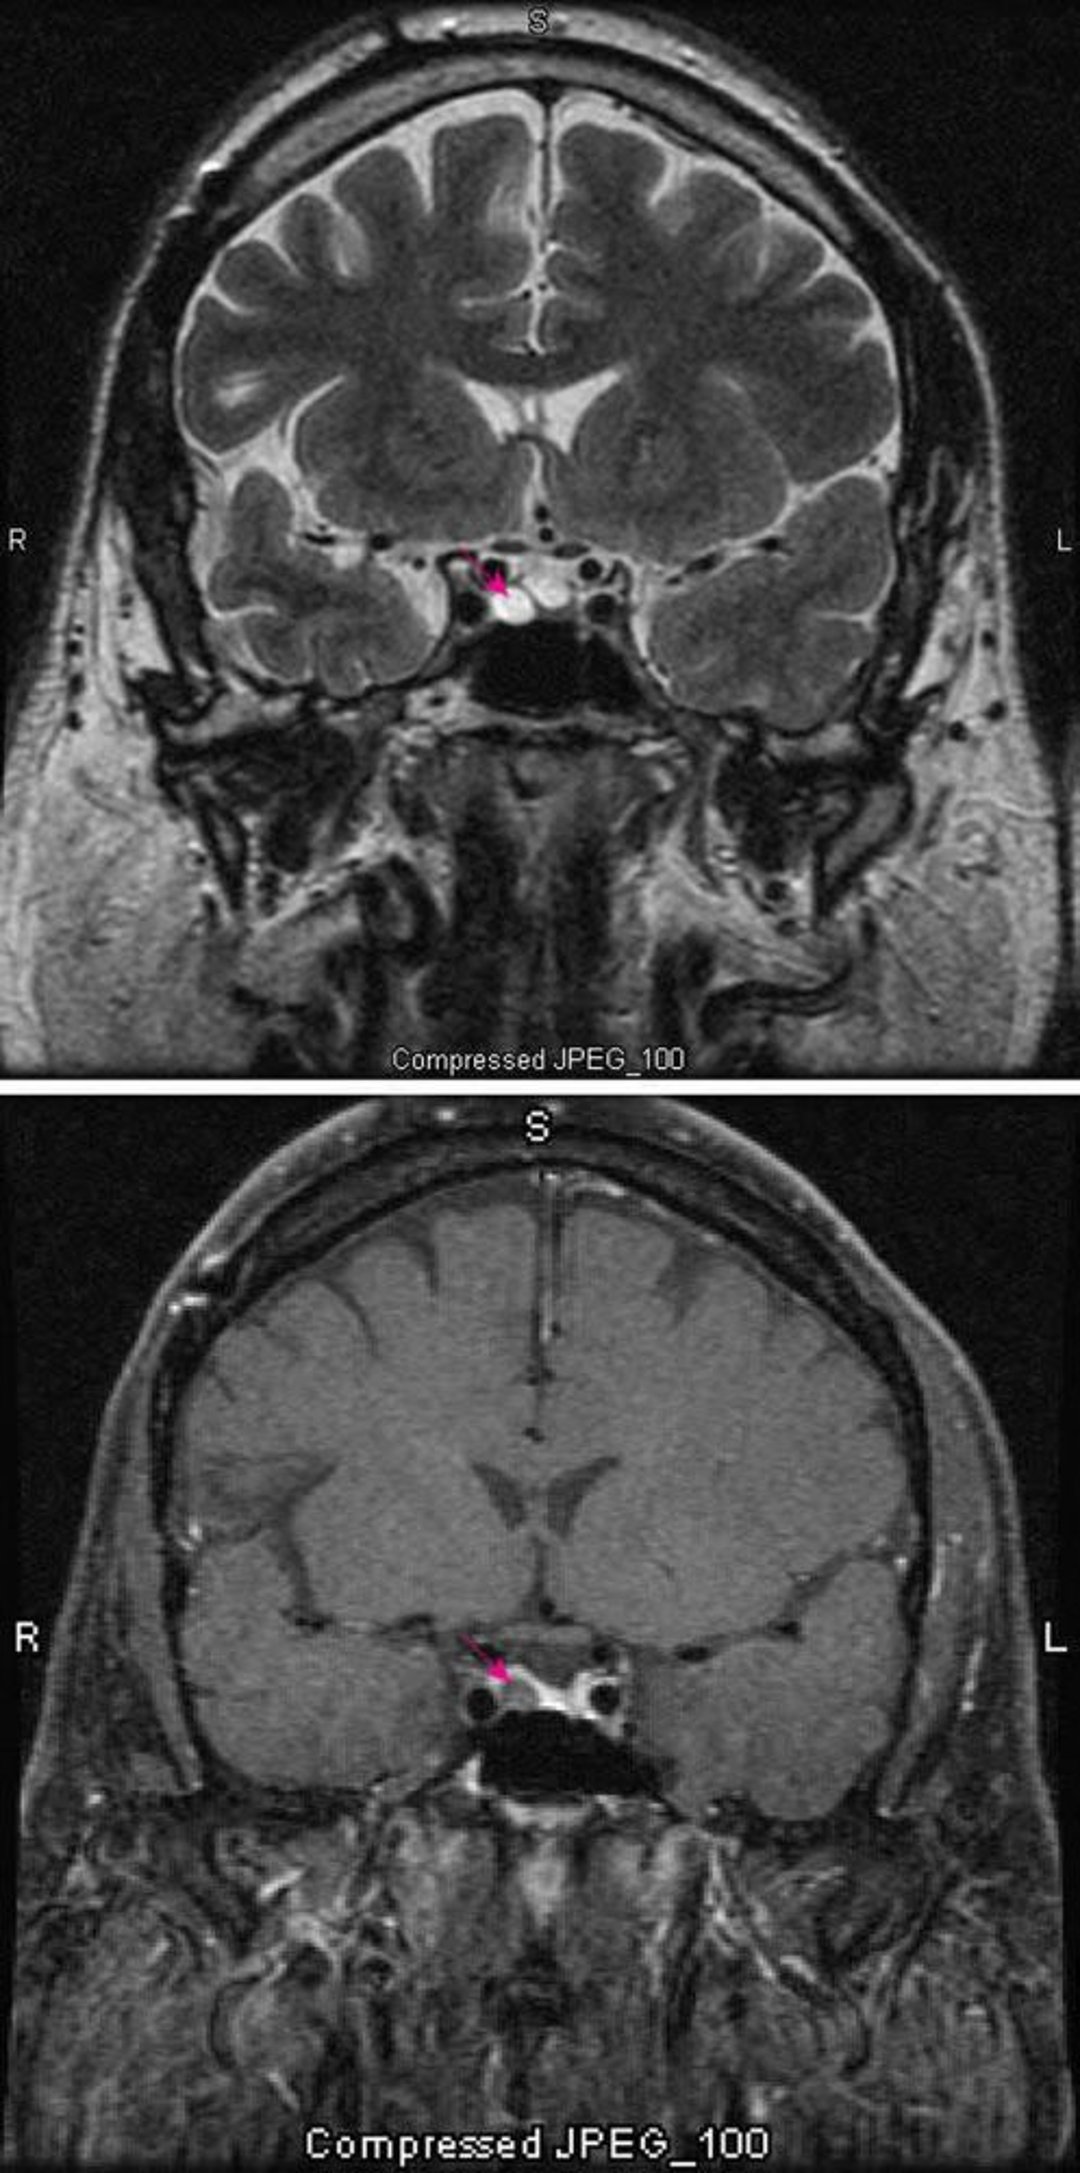

Microadenoma ipofisario

La sequenza T2 pesata di RM (in alto) mostra un microadenoma ipofisario (freccia rossa). Il contrasto (in basso) normalmente evidenzia l'ipofisi (freccia rossa). L'adenoma appare più chiaro.

Images courtesy of William R. Shapiro, MD.